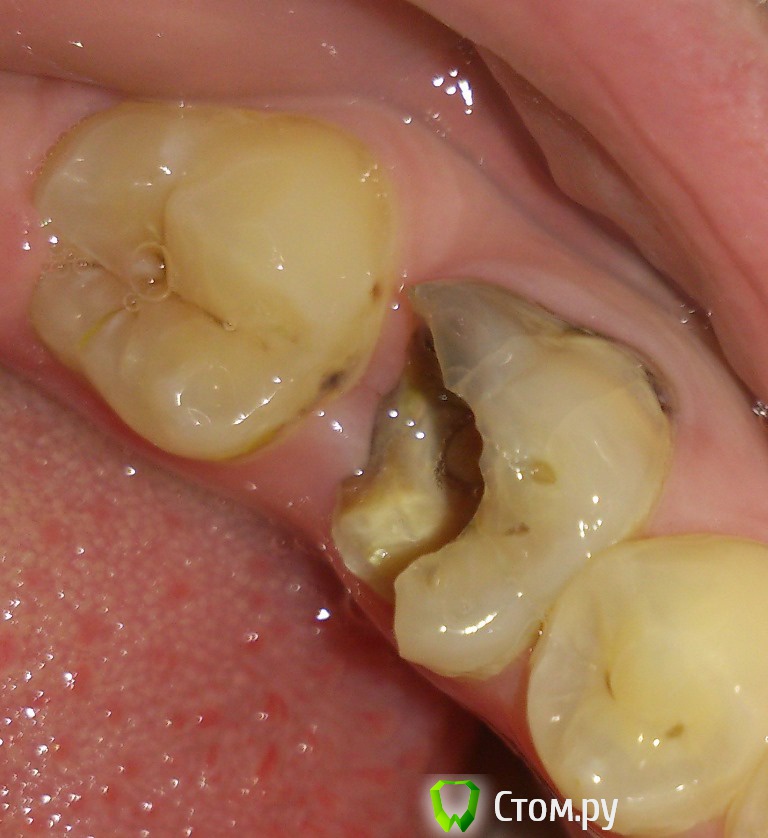

sunbeam Опубликовано 3 июля, 2014 Автор Поделиться Опубликовано 3 июля, 2014 Добрый день, прикрепляю прицельный снимок 3.6 и фото, насколько его удалось сделать. Врач предложила перепломбировать каналы и восстановить зуб пломбой.В моем представлении такой большой зуб пломбой восстановить несколько ненадежно,нужен по крайней мере штифт, чтобы пломба не отвалилась из-за мармеладки, как в прошлый раз. Так как я не специалист, очень хотелось бы мнений. Ссылка на комментарий

red_butler Опубликовано 4 июля, 2014 Поделиться Опубликовано 4 июля, 2014 Перелечить корневые каналы, далее корневая вкладка и коронка. И откладывать уже не куда 1 Ссылка на комментарий

IvanK Опубликовано 4 июля, 2014 Поделиться Опубликовано 4 июля, 2014 + 1 , еще чуть-чуть и на удаление Ссылка на комментарий